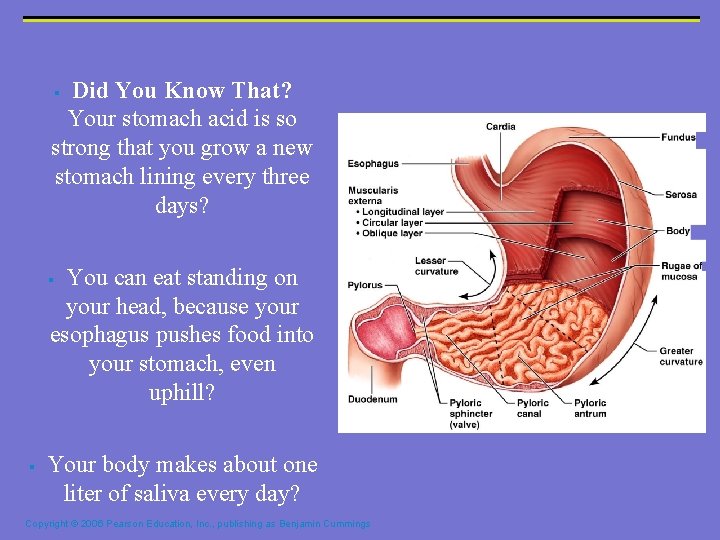

Did You Know That? Your stomach acid is so strong that you grow a new stomach lining every three days? § You can eat standing on your head, because your esophagus pushes food into your stomach, even uphill? § § Your body makes about one liter of saliva every day? Copyright © 2006 Pearson Education, Inc. , publishing as Benjamin Cummings

Digestion in the Stomach § The stomach: § Holds ingested food § Degrades this food both physically and chemically § Delivers chyme to the small intestine § Enzymatically digests proteins with pepsin Copyright © 2006 Pearson Education, Inc. , publishing as Benjamin Cummings